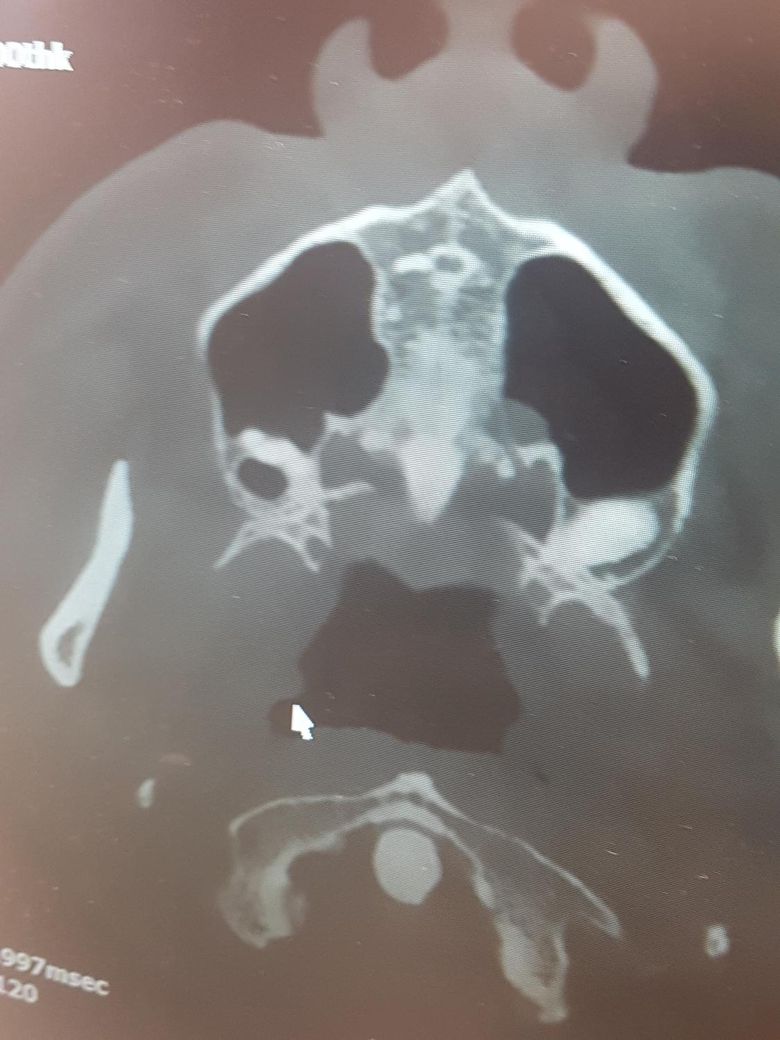

위쪽 사랑니 상악동 천공 확률 질문입니다.

그런데 파노라마는 물론이고 CT 촬영했을때도 저 정도로 사랑니가 들어가있다네요.

1.상악동 천공 날 확률이 높을까요? 아니면 천공 안나게 뽑는 방법도 있을려나요?

2.천공이 터져도 저 정도면 잘 아물까요?

3.혹시 상악동 CT로 축농증 판단이 가능한가요? 일단 아니라고 판단받긴했는데 이비인후과에선 코내시경으로 축농증 판단을 내려줘서...

1,천공될 가능성 있지만 그래도 뽑는 것을 추천합니다.

1. 설령 천공 된다고 해도 이런 천공은 99%저절로 막힙니다.

2. CT 에서 축농증 소견 안보이며 깨끗한 상악동입니다.

상악동 천공이 생길 수 있으나 따로 방법이 있는 것은 아닙니다. 보통은 금방 아물게 됩니다.

상악의 경우는 잇몸뼈가 많이 단단하지 않아서 천공될 확률이 크게 높진 않습니다. 그리고 천공이 되더라도 특별한 문제가 없다면 시간이 지나면 자연스럽게 괜찮아 집니다.

일단, 판단 시 CT에서 저 view 말고 정면 view가 좀 더 나을 것 같습니다.

사랑니가 아주 상악동에 근접하건, 함입되어 있다면 발치 시 천공 가능성 있으나 큰 천공일 경우 처치해줍니다 걱정하지 않으셔도 됩니다.

축농증 관련 점막 비후의 경우에는 이비인후과 의사의 판단이 좀 더 전문적일 수도 있습니다.